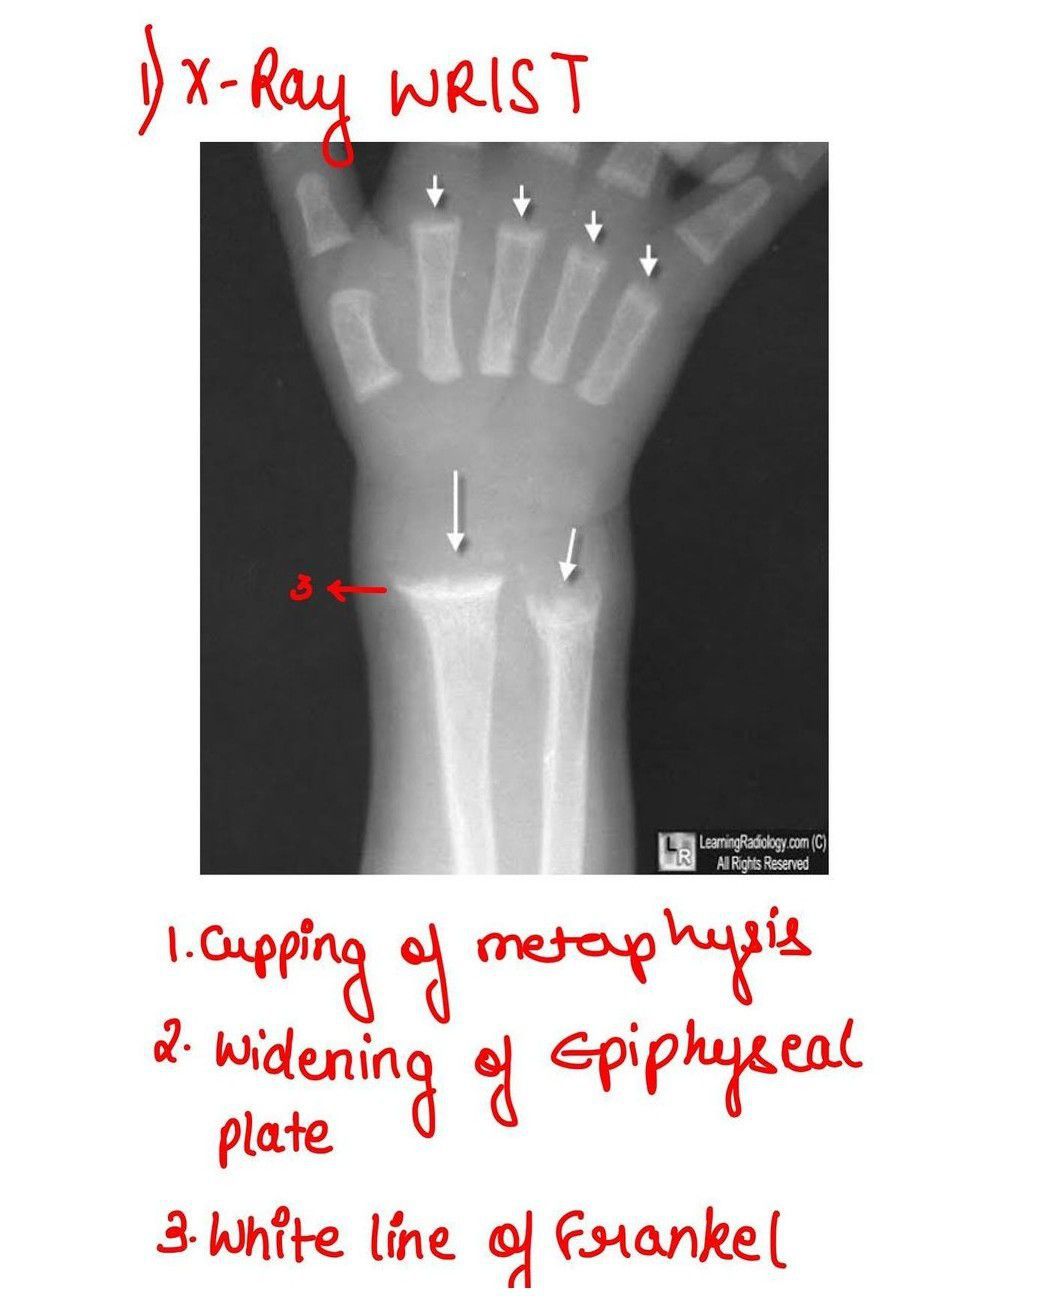

Rickets - X-ray Wrist

This is the radiological feature of rickets.